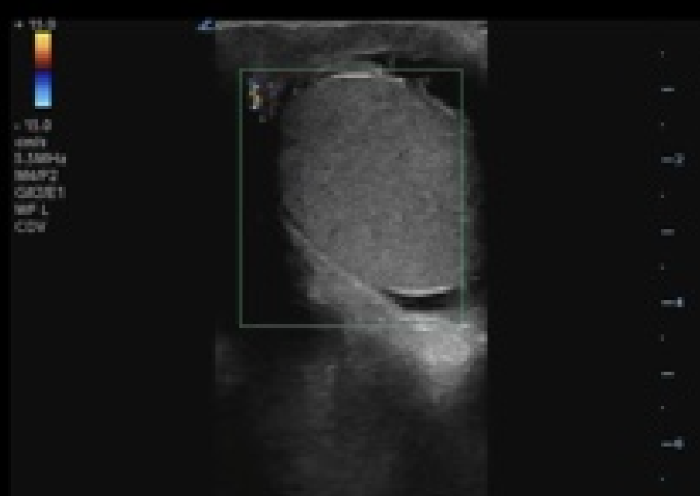

In your first image (Image 1), you realize there is no flow with color Doppler. Additionally, you find a torsed cord complex (Image 2), also known as the “corkscrew sign.” You consult Urology who is busy in the operating room with another case. You decide to perform a manual detorsion due to your concern for testicular atrophy and risk of infertility. Using the open book technique, you get relief of pain and return of vertical positioning of the testicle after two rotations. On your repeat testicular POCUS with color Doppler you obtain these images (Images 3 and 4), which demonstrate venous and arterial flow throughout the testicle. The cord is now untwisted and appears linear in orientation.

Torsion - image 4_crop.pngImage 4. Linear, untwisted appearance of the spermatic cord with accompanying vessels.

The Cord

The spermatic cord can be found at the superior pole of the testicles. Although included in this article after the affected testicle, it should be scanned after each testicle. The normal spermatic cord should have a linear appearance with an accompanying vessel demonstrating blood flow with color Doppler.9